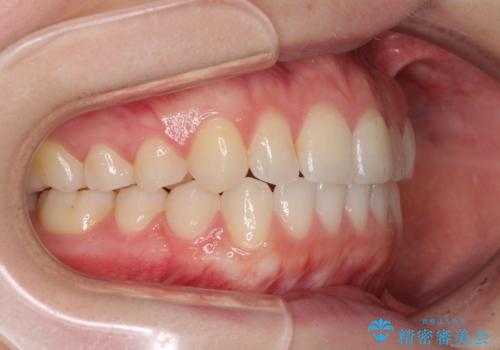

前歯のクロスバイトをインビザライン矯正で改善

- 前歯のデコボコと上下のクロスバイトを気にして来院された患者様です。

インビザラインを用い、IPR(歯と歯の間を削る)と歯列全体を拡大させることで、歯並びを整えていくこととしました。

上の前歯が下の前歯を乗り越える際、奥歯がほとんど咬めない時期があり、乗り越えた後も、インビザライン特有の奥歯の咬みにくさが続きました。

咬み合わせ改善のために治療期間を要しましたが、最終的に奥歯はしっかりと咬めるようになりました。